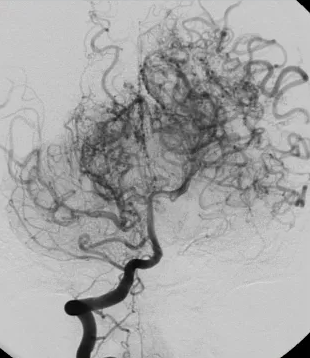

“모야모야병”이라는 이름은 일본어 ‘모야모야’(연기가 뿌옇게 피어오르는 모습)에서 유래했어요.

즉 뇌 속 혈관이 점점 좁아지면서, 부족한 혈류를 보충하려 작은 비정상 혈관들이 솟아오르는 모습을 연상케 해서 붙여진 이름이예요.

이 병은 만성 뇌혈관 질환의 하나로, 뇌에 혈액을 공급하는 주요 혈관들이 서서히 좁아지거나 폐색되고, 뇌 저류 부위에 비정상적 측부(우회) 혈관이 발달하는 특징이 있어요.